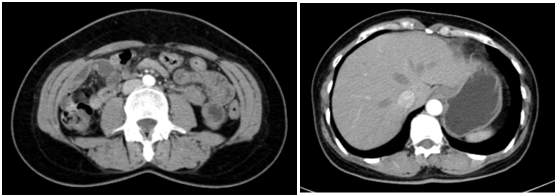

Cắt lớp vi tính lồng ngực:

Hình 2: Hình ảnh cắt lớp vi tính lồng ngực chưa phát hiện bất thường

Cắt lớp vi tính ổ bụng:

Hình 3: Hình ảnh cắt lớp vi tính ổ bụng chưa phát hiện bất thường